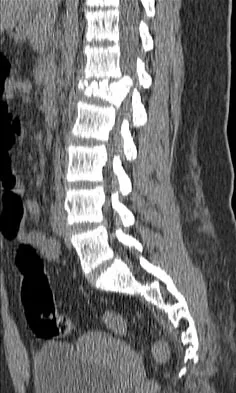

Figures 9a and 9b show the spinal radiographs of a 3-year-old child with short limb dwarfism. The lateral radiograph is obtained with maximal lumbar extension. Management should consist of

The patient has kyphosis in association with achondroplasia. The AP radiograph shows decreased interpedicular distance at the lower lumbar vertebrae, a feature considered to be a distinctive sign of achondroplasia. Most patients with achondroplasia have kyphosis, and this usually resolves spontaneously. When the fixed component is greater than 30 degrees, however, brace treatment is recommended. Spinal fusion is seldom required.